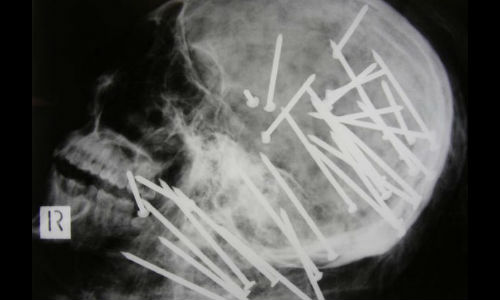

ഉഗ്രശേഷിയുള്ള നെയില് ഗണ് പൊട്ടി ആണികള് തറച്ച ചൈനക്കാരന്റെ തലയോട്ടിയാണ് എക്സ്-റേയില് തെളിയുന്നത്.